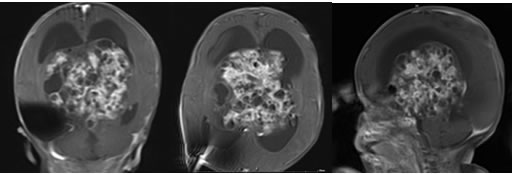

头增强MRI检查结果:第三脑室占位性病变,脑积水。

入院诊断:颅内生殖细胞肿瘤(未成熟/恶性畸胎瘤?内胚窦癌/含内胚窦成分的混合生殖细胞肿瘤?)、梗阻性脑积水。

治疗方案讨论:1、患儿肿瘤恶性程度高,预后差;2、患儿体重不足5kg,肿瘤体积较大,术中出血致失血性休克发生率高,手术难度大,对术者手术技术及手术时间都是极大挑战;3、术后出现下丘脑损伤、内分泌紊乱、电解质紊乱等并发症较多;4、家属表示不放弃治疗,愿承担一切风险接受治疗延长患儿生存期。